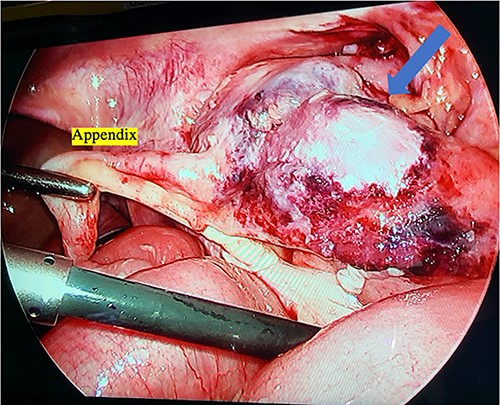

Right leg fasciotomy and debridement were performed by an orthopedic surgeon; there was evidence of ischemia to the distal gastrocnemius. A diagnostic laparoscopy was then performed, which revealed a normal liver and extensive adhesions. She was found to have free fluid and an ischemic terminal ileum, which extended to the cecum and ascending colon (Fig. 4). Given these findings and her clinical status, an ileocolic resection with an end ileostomy was performed. Postoperatively, she returned to the Pediatric Intensive Care Unit. Her intra-abdominal fluid and deep leg swab cultures were positive for C. septicum, and her antibiotics were switched to ceftriaxone and metronidazole. She improved and was gradually weaned off ventilatory and cardiovascular supports. She returned to the operating room for closure of her fasciotomies 3 days following her initial surgery. She required three more surgical debridements of her right leg over the course of the next 2 months of her admission.

Intraoperative photograph of the ileocecal junction with extensive inflammation and necrosis.